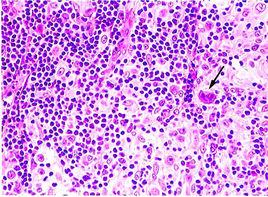

淋巴瘤可分為以下兩類,並在此作個比較!

何杰金氏病 非何杰金氏病

好發年齡層 較常發生在年輕人,及45歲以上的中老年人。 多發生在五歲以後,且各年齡層均可能,男多於女。

發生機率 10%(且台灣較少見) 90%(國人罹病常屬此種)

發展速度及臨床分期 :較慢,診斷時,病變範圍較小,分為4期。 較快,診斷時,病變範圍較廣,分為4期。

擴散方式 主要通過淋巴道附近的淋巴結擴散 通過淋巴道或血液的循環,向鄰近或遠 淋巴結,及其結外組織擴散。

侵犯結外組織 少,發生較晚 常見,較早發生

合併白血病 極少 較多見

治療效果 比較恆定 部份病例較差